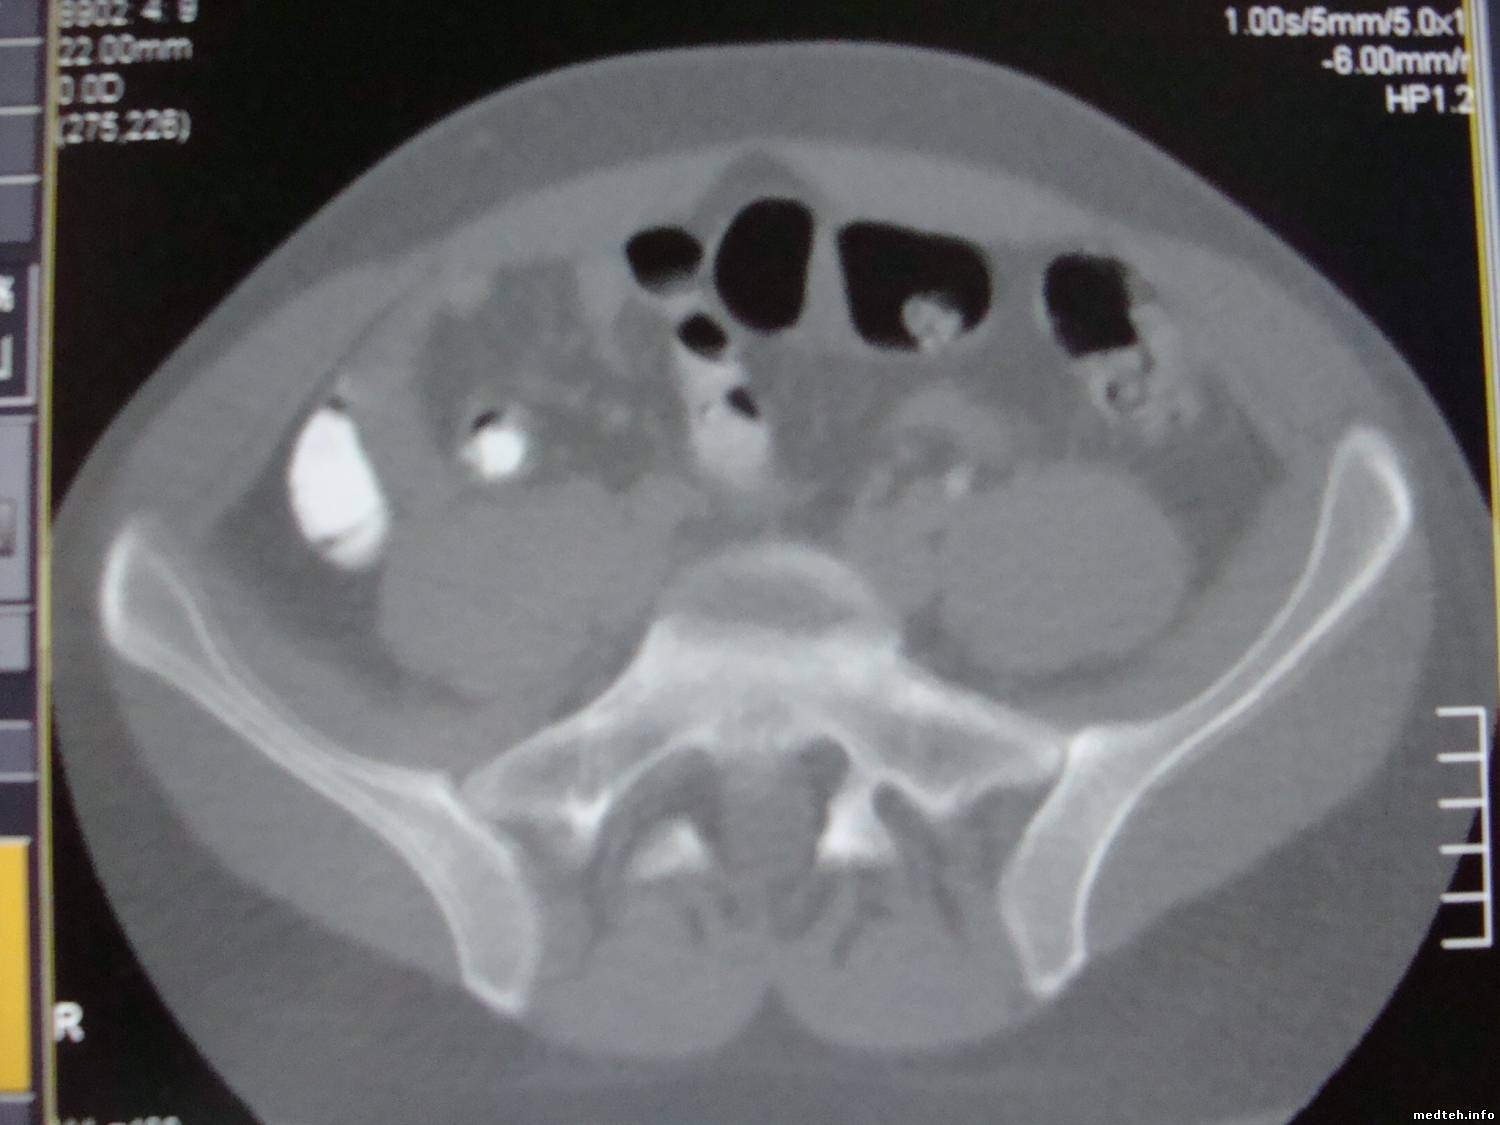

А вот и фото.

Если кому интересно.

Как видно - присутствует элемент двоения, например кости, слева, на картинке.

8035747.jpg (104.1 Kb)